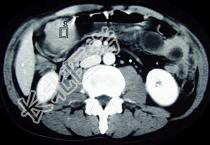

- 单项选择题女性,42岁, 腹痛、黑便1周,CT扫描见胃窦部圆形块影, 最佳的诊断是  (    )